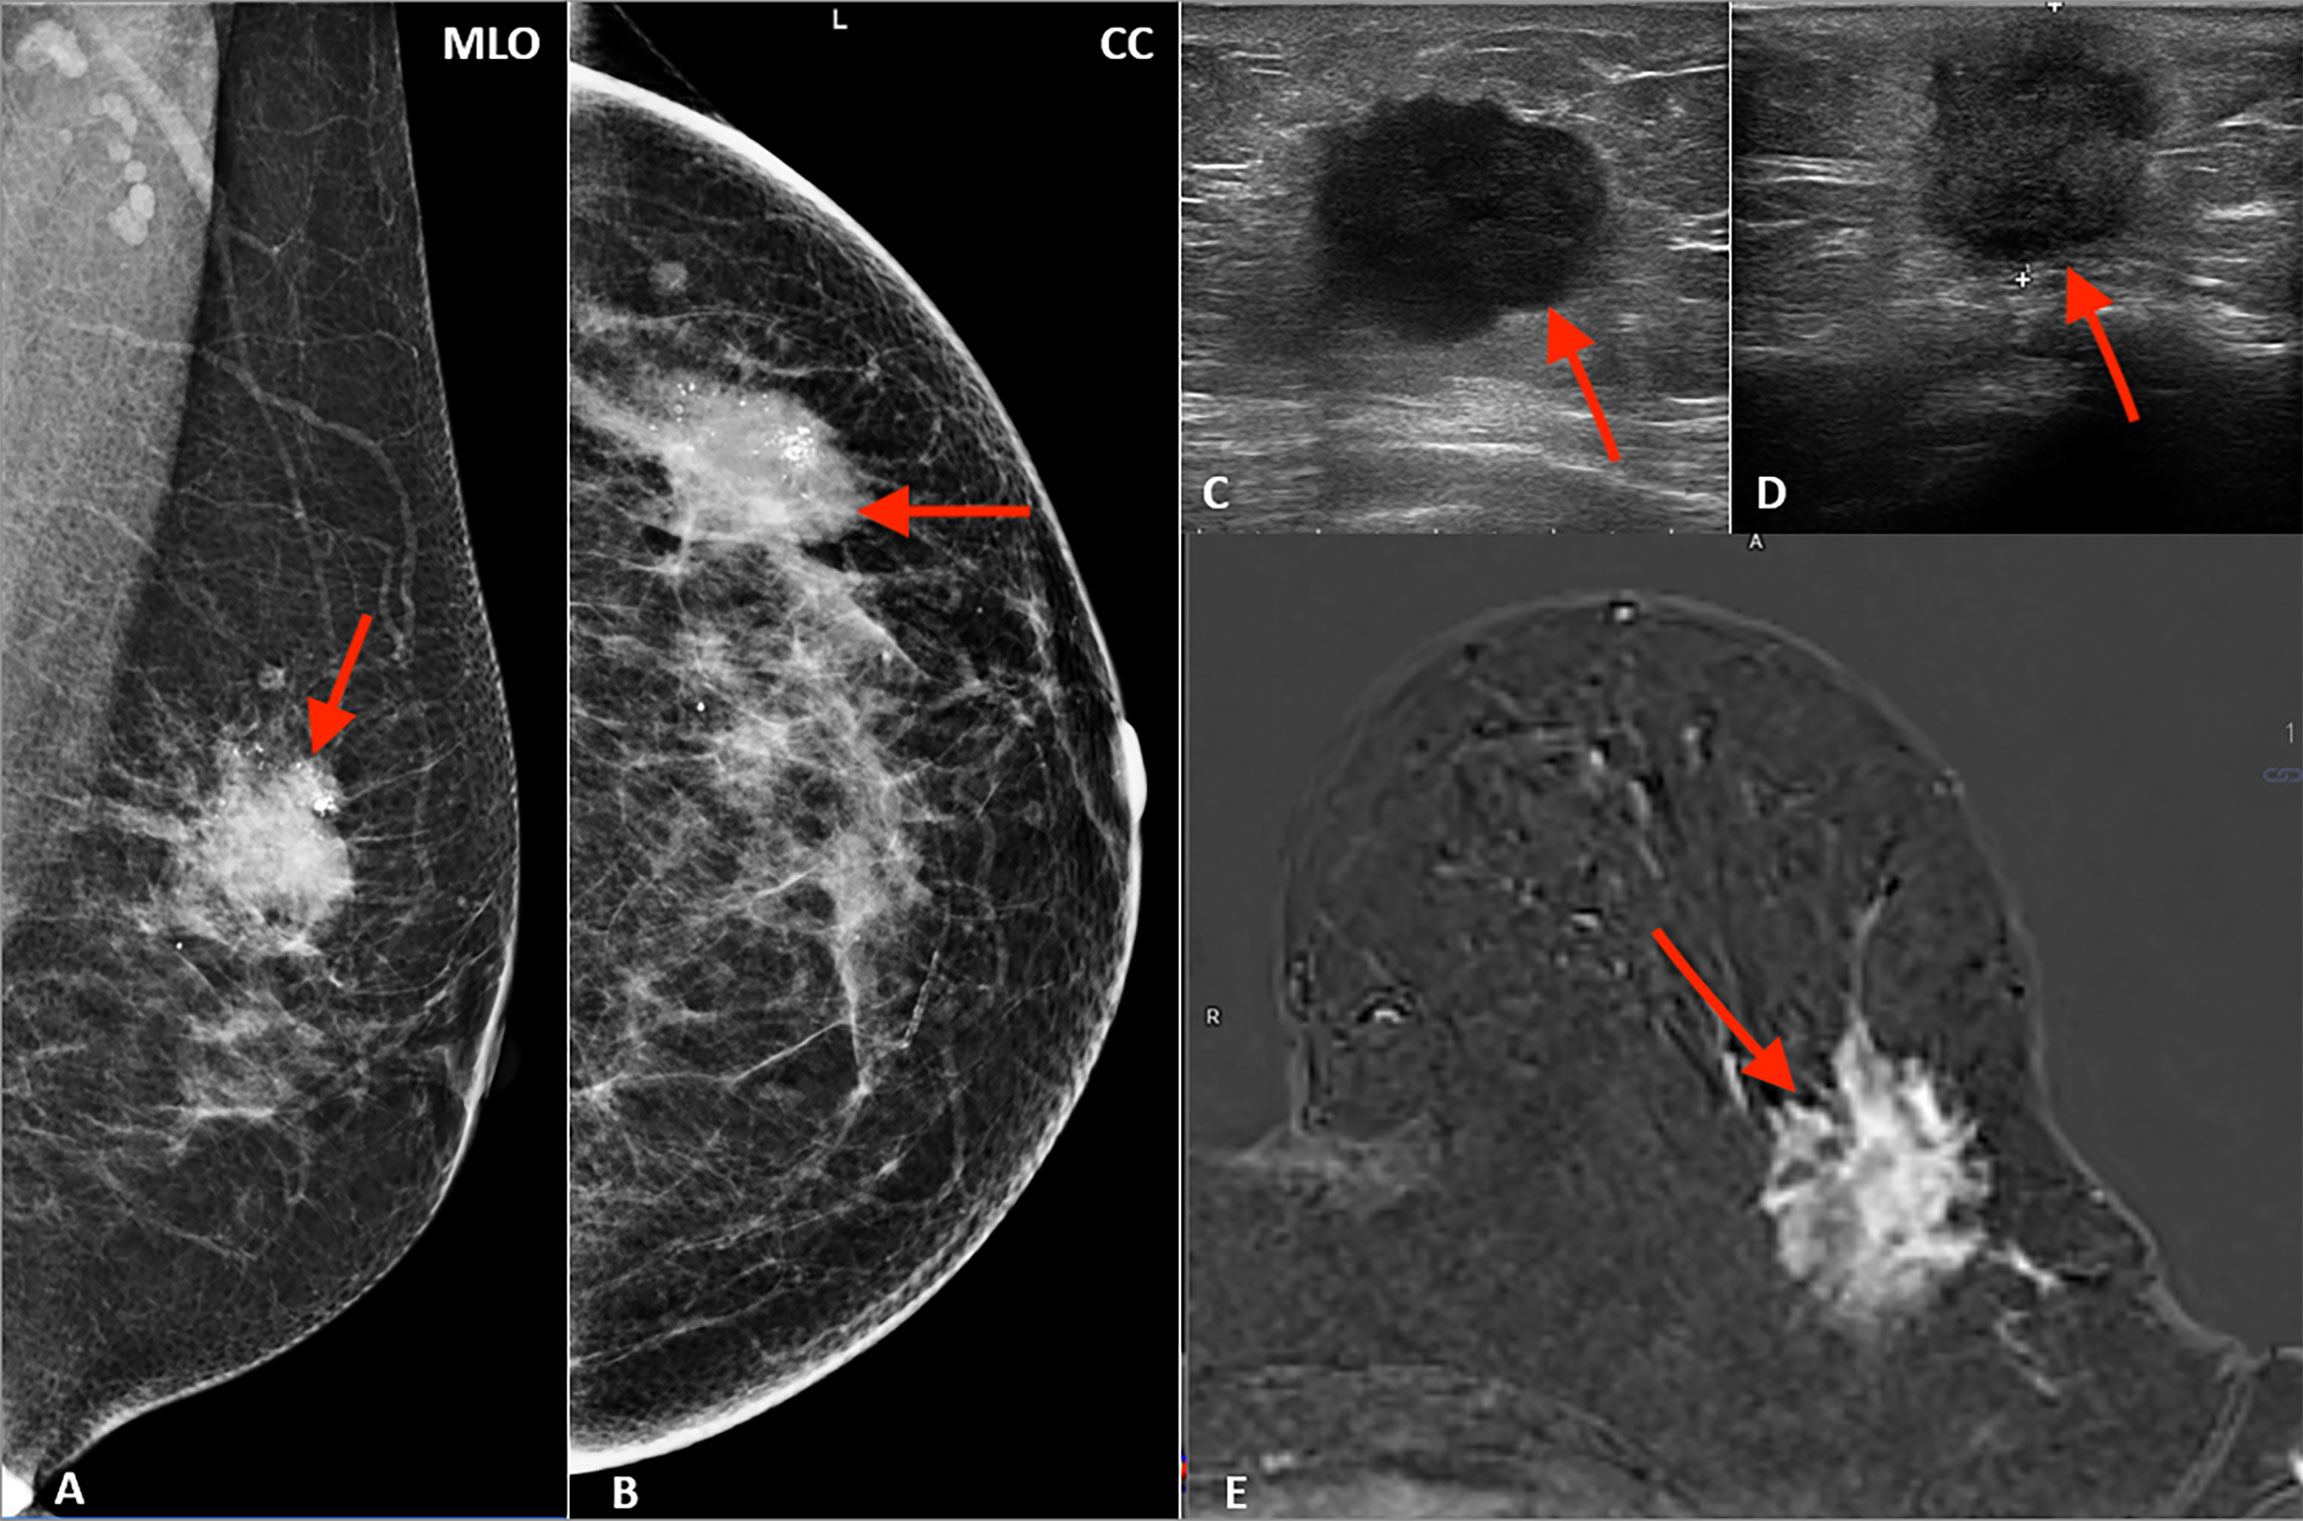

Understand the early warning signs of colorectal health with this informative guide. Featuring a detailed cancer du colon image, we break down essential symptoms, screening methods, and diagnostic procedures. Learn how early detection through colonoscopy and awareness of digestive health factors can significantly improve treatment outcomes. Stay informed about risk factors and prioritize your long-term wellness today.